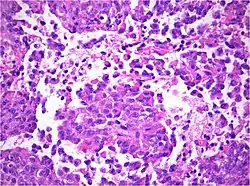

Obraz histologiczny

AT/RT jest guzem bogatokomórkowym, o rozlanym typie wzrostu. Często stwierdza się przegrody łącznotkankowe oddzielające grupy komórek. W przypadkach gdy naciek nowotworowy obejmuje powierzchnię mózgowia stwierdza się niekiedy izolowane grupy komórek w oponach, prawdopodobnie będące wszczepami nowotworowymi. AT/RT jest bardzo aktywny mitotycznie.

Profil immunohistochemiczny

Komórki AT/RT dają odczyn dodatni na ekspresję wimentyny, NSE, EMA, cytokeratyn, GFAP, S-100, synaptofizyny, aktyny mięśni gładkich i neurofilamentów. Ekspresja antygenu Ki-67 pozwala ocenić aktywność proliferacyjną guza na nawet 80%.